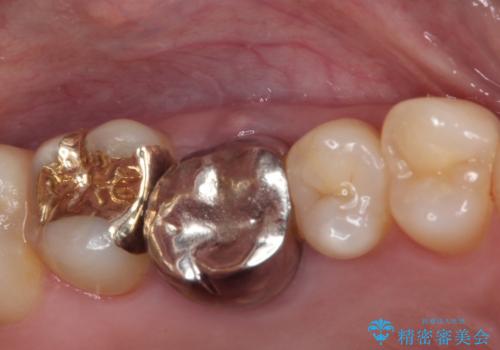

- 前歯などに、むし歯でボロボロになった歯があるとのことで来院された患者様です。

むし歯により歯冠が崩壊してから長いこと経過しているとのことで、歯を失ったことによる他の歯への影響はあまりないと判断されたため、審美領域である上顎前歯部のみにインプラント補綴治療を行うこととしました。

2本の歯が前後に重なった状態でむし歯となっていたので、抜歯後に歯肉や骨の状態が落ち着くのを待ち、インプラントを埋入することとしました。